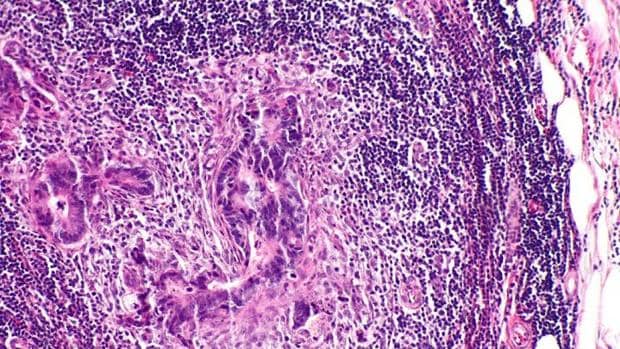

Para responder a esta pregunta, los autores analizaron más de 200 muestras de tejidos de los tumores primarios, metástasis ganglionares y metástasis distantes de 17 pacientes con cáncer colorrectal. Y lo que hicieron fue analizar la presencia de unos segmentos repetidos –segmentos de poliguanina o ‘Poli-G’, muy susceptibles a sufrir mutaciones– en el genoma de las células tumorales para, así, identificar el ‘origen’ de las células metastásicas.